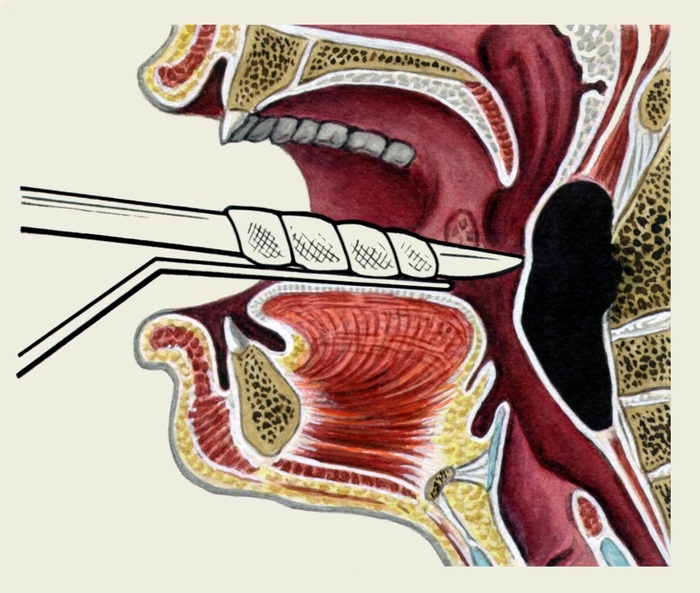

Выявленный заглоточный абсцесс подлежит хирургическому вскрытию и дренированию. В месте наибольшего выбухания делают разрез абсцесса скальпелем или остроконечными ножницами. В разрез вводят наконечник электрического отсоса и отсасывают гной. Важно сразу же после вскрытия заглоточного абсцесса быстро произвести отсасывание гноя, чтобы избежать его попадания в дыхательные пути. Для предупреждения затекания гноя в дыхательные пути в момент вскрытия абсцесса некоторые авторы рекомендуют предварительно производить его пункцию и отсасывать гной. В некоторых случаях после вскрытия заглоточного абсцесса края произведенного разреза слипаются, тогда прибегают к их повторному раздвиганию с использованием желобоватого зонда или щипцов Гартмана.